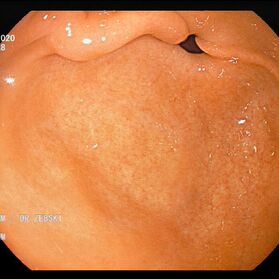

Mit einer Gastroskopie werden Speiseröhre, Magen und Zwölfingerdarm (der oberste Teil des Dünndarms) untersucht. Dazu wird ein geschmeidig biegsames, schlankes Endoskop mit eingebauter Digitalkamera durch den Mund eingeführt. Minimalste Veränderungen können dabei gesehen werden, die im Röntgenbild oder einer Kernspintomographie (MRT) noch gar nicht erkannt werden. Im Vergleich zu anderen bildgebenden Untersuchungsverfahren ist bei der Endoskopie neben der wichtigen optischen Beurteilung auch die sofortige Möglichkeit gegeben, Gewebeproben aus auffälligen Bereichen zu entnehmen. Dazu wird eine kleine Spezialzange durch einen Kanal im Endoskop geschoben und die Probe ganz präzise aus dem entsprechenden Gewebe gewonnen. Da die Schleimhäute schmerzunempfindlich sind, spüren Sie davon nichts. Die Proben werden von Spezialisten mikroskopisch untersucht und ermöglichen dann eine zielgerichtete Therapie; zum Beispiel wenn eine Magenschleimhautentzündung durch eine chronische Infektion ausgelöst wird, die mit einer Antibiotikakur erfolgreich behandelt werden kann.